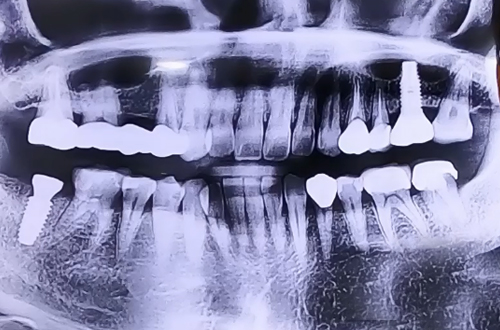

오른쪽 아래 큰 어금니 통증이 심한 사례

BEFORE

치아가 반으로 깨진 상태로 방문하신 환자분이십니다.

꺠진 곳 안쪽으로 충치가 생기고 이가 약해져 있는 상태에서

음식을 씹을 때 쎈 힘을 견디지 못하고 깨진 상태인데요.

통증이 굉장히 심하셔서 바로 발치한 뒤에 임플란트를 진행해 드렸습니다.

임플란트를 바로 심었기 때문에 뼈들이 임플란트를 단단하게

둘러쌀 수 있도록 뼈이식을 통해 진행해 드린 후 임플란트

위쪽으로 이를 뺀 구멍을 메울 수 있는 뚜껑으로 덮어 놓고

4개월 후 주변 뼈들이 굳고 나면 위쪽에 큰 어금니를 제작할 계획입니다.